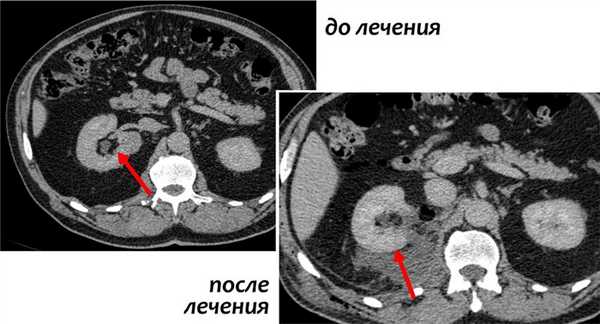

При МСКТ в нижнем сегменте правой почки экстраренально определяется округлое образование диаметром 3 см, неоднородной повышенной плотности, с четкими ровными контурами, не накапливающее контрастный препарат (плотность до контрастирования 63 ед.Н., после контрастирования 64 ед.Н) - осложненная киста (рис. 2). В верхнем сегменте левой почки киста 1,5 см, в среднем ангиомиолипома до 1,8 см в диаметре.

Рис. 2. Мультиспиральная компьютерная томография (МСКТ) - стрелкой указано образование в нижнем сегменте правой почки.